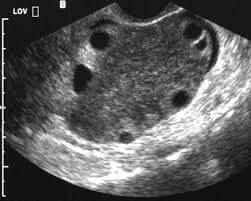

Ultrasound usually shows an enlarged ovary with peripherally displaced follicles, free fluid is often present, no Doppler flow is also often seen (early torsion can still have arterial flow, with venous and lymphatic drainage absent, also the ovary may spontaneously detorse).

Sonographic findings

- Unilaterally enlarged ovary

- Peripherally displaced follicles due to edema

- Coexistent mass

- Twisted pedicle (not always seen)

- Free fluid